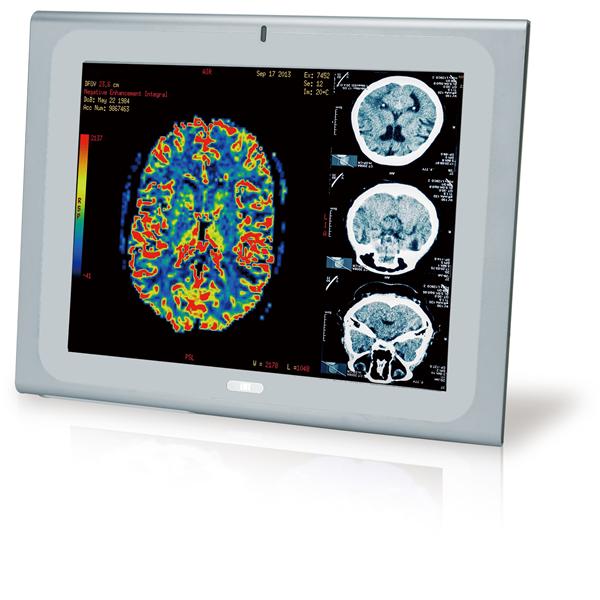

IEI Technology | Panel PCs 17" Medical Pan... |

Get Quote | |||

IEI Technology | Panel PCs 19" Medical Pan... |

Get Quote | |||

IEI Technology | Panel PCs 17" Medical Pan... |

Get Quote | |||

IEI Technology | Panel PCs 19" Medical Pan... |

Get Quote | |||

IEI Technology | Panel PCs 17" Medical Pan... |

Get Quote | |||

IEI Technology | Panel PCs 19" Medical Pan... |

Get Quote | |||